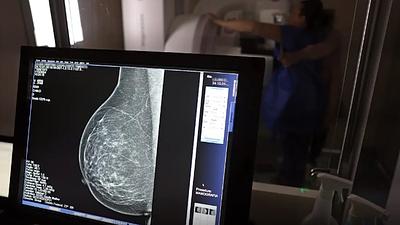

Maricá anuncia fim da fila de mamografias durante Outubro Rosa

Credenciamento de clínicas parceiras e unidades móveis permitiram realização de 13 mil exames este ano, atendendo demanda de duas mil mulheres.

A mamografia é um exame de fundamental importância para diagnóstico precoce e redução da mortalidade. Em 2020, foram 22.159 exames realizados no Rio Imagem e em outras unidades da rede estadual de saúde.